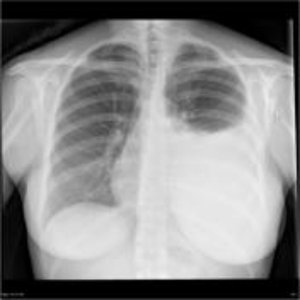

Recurrent Fluid Accumulation

Repeated build-up of fluid in the abdomen, chest, or around organs causing breathlessness, discomfort, or infection.

Recurrent Cancer-Related Fluid Collections

Ascites, pleural effusion, or abscesses requiring repeated

drainage.